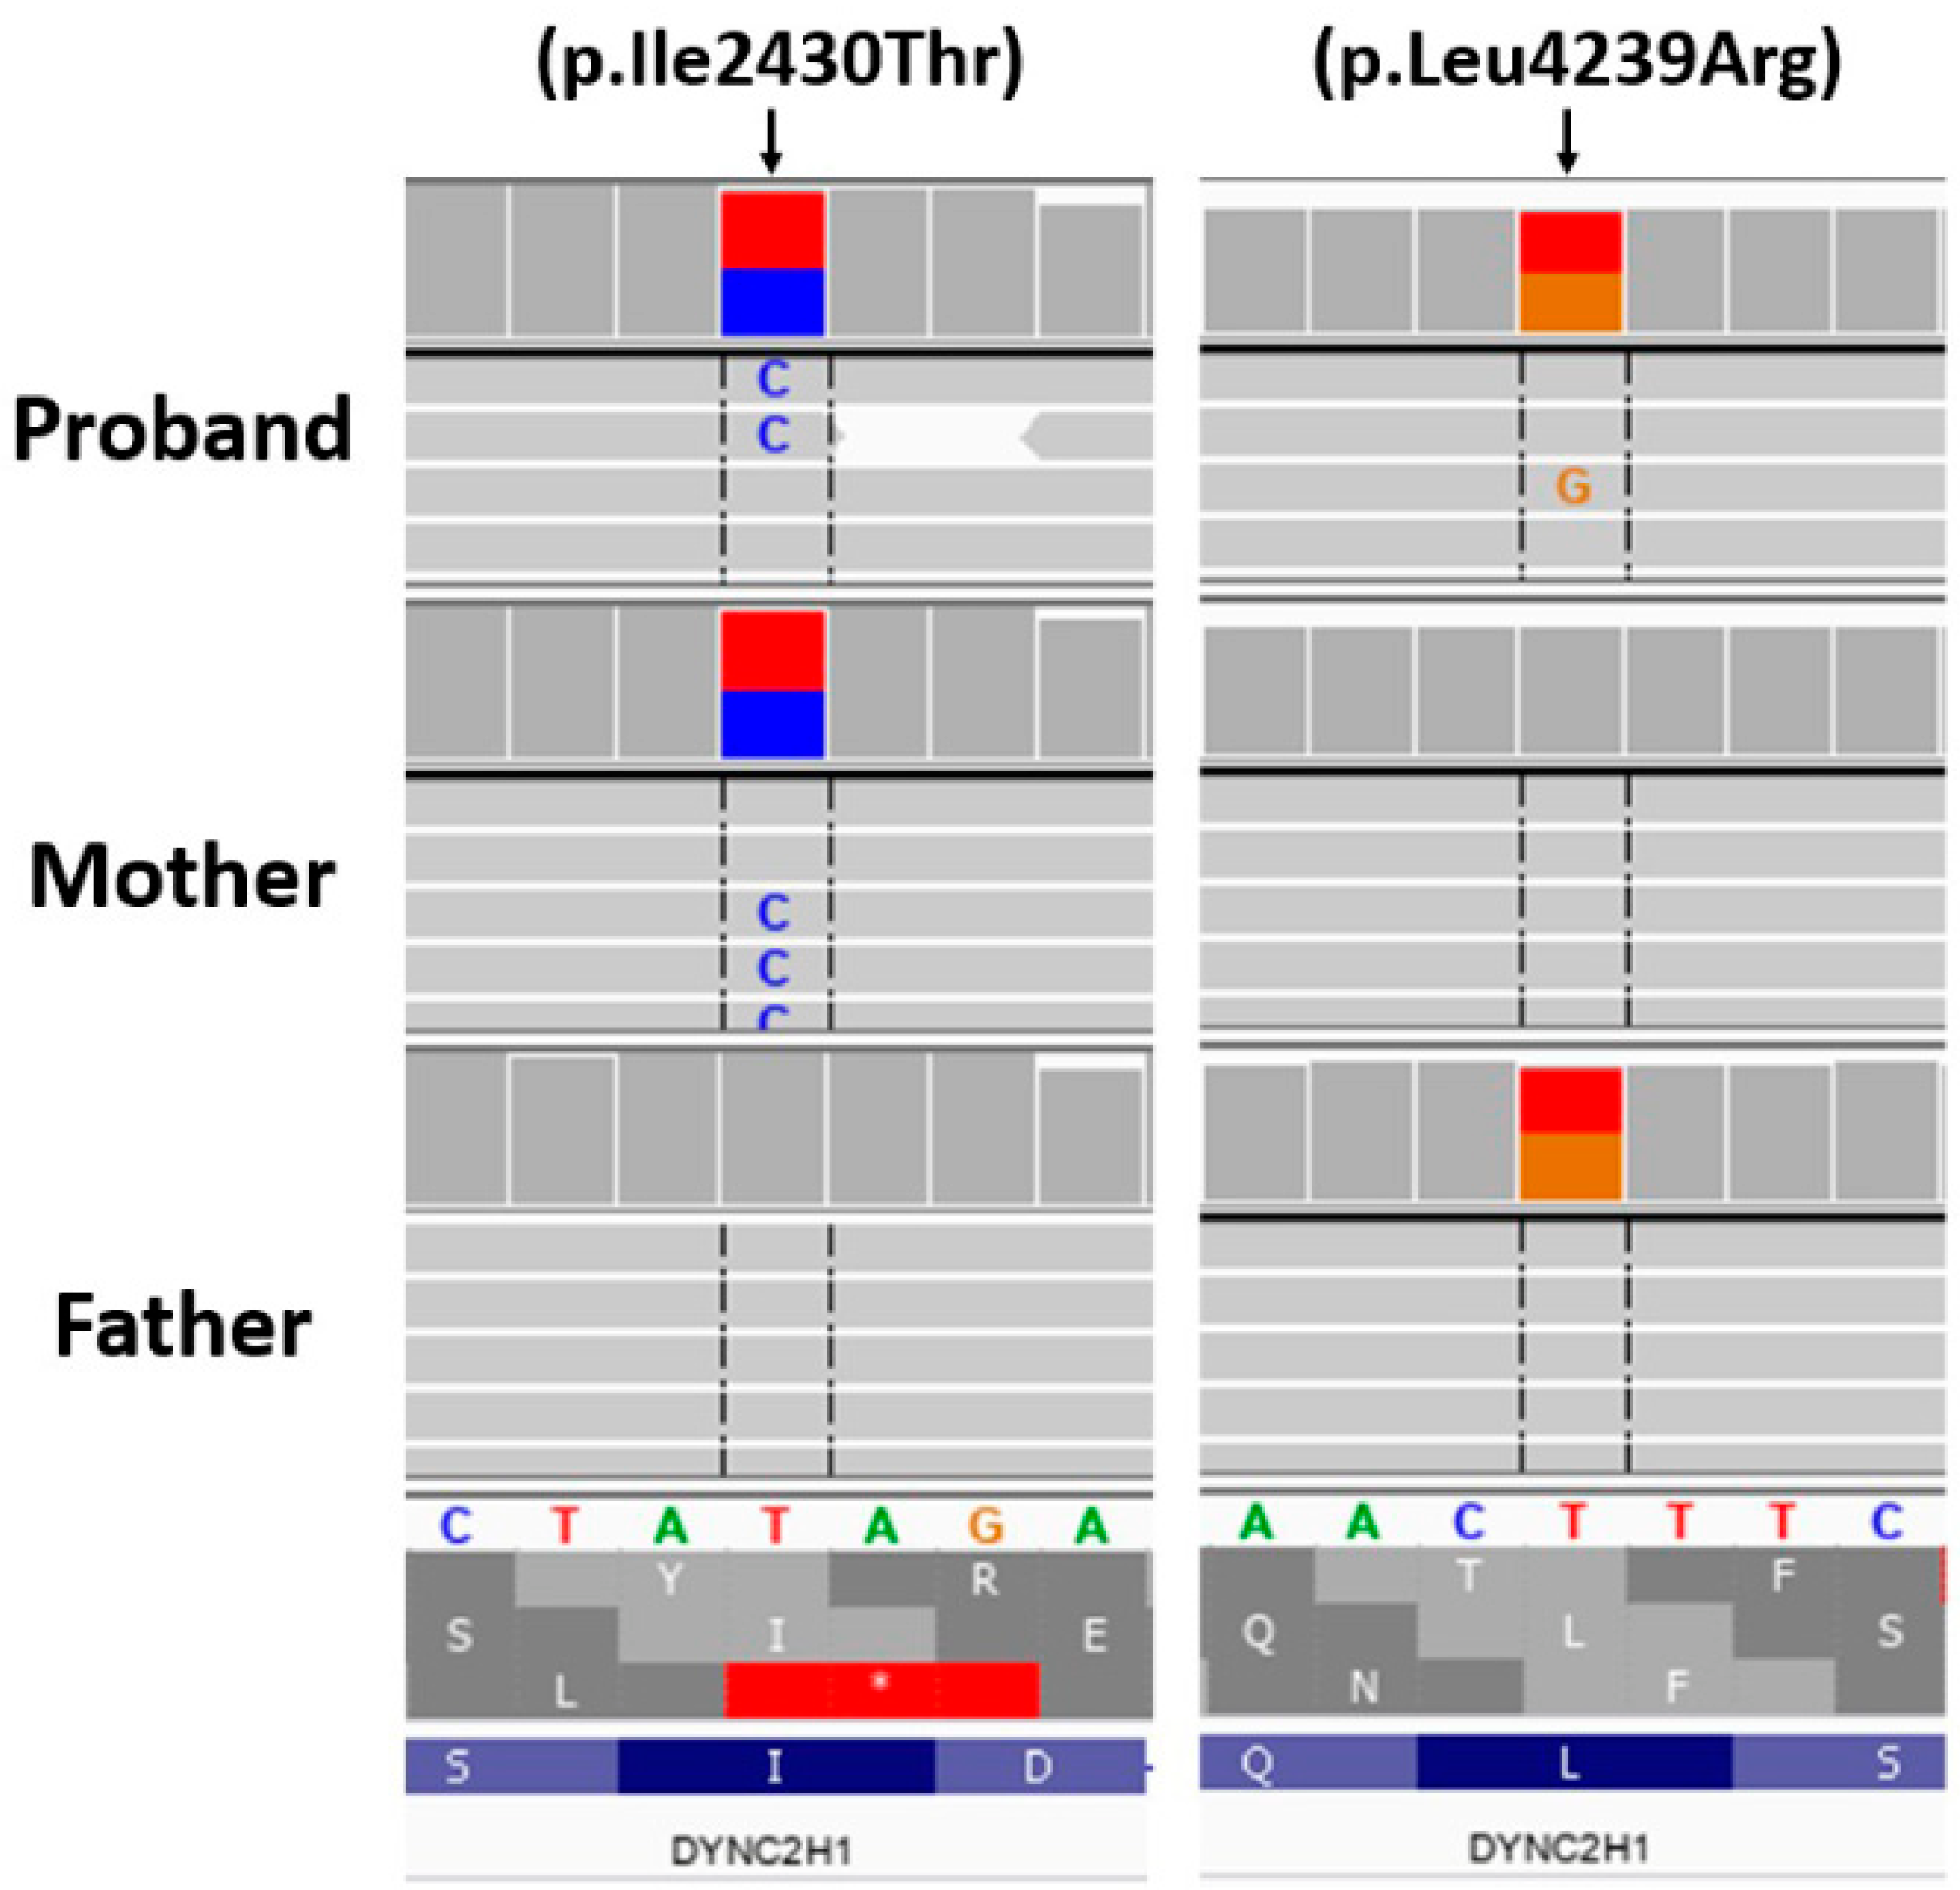

3. Genetic Testing

4. Results